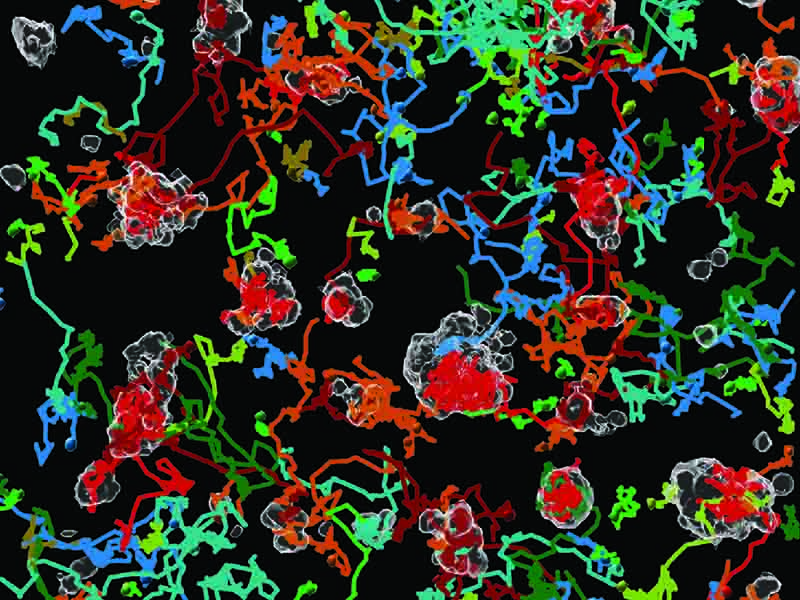

Cuando se colocan las muestras en un cultivo, se les añaden marcadores, diferentes colorantes fluorescentes, lo que facilita seguir el destino de las distintas células y captar cómo los linfocitos T atacan a las células tumorales, y cuál es su comportamiento en dicho proceso.

La información, una vez procesada, aporta una ingente cantidad de datos resultado de la monitorización. La parte de visualización del proceso se realiza gracias a la técnica de imagen de microscopía confocal tridimensional, la especialización de la investigadora Alieva antes de transitar hacia el análisis de datos masivos. El modelo 3D permite “observar el proceso de una forma en la que, si una célula tumoral está encima de un órgano, no quede oculta por él, algo que en una fotografía 2D podría suceder”, aclara la científica. Una metodología que, debido al tamaño de las imágenes y el seguimiento de las trayectorias de las células, tiene el inconveniente de que se trata de un trabajo costoso a nivel de procesamiento computacional.